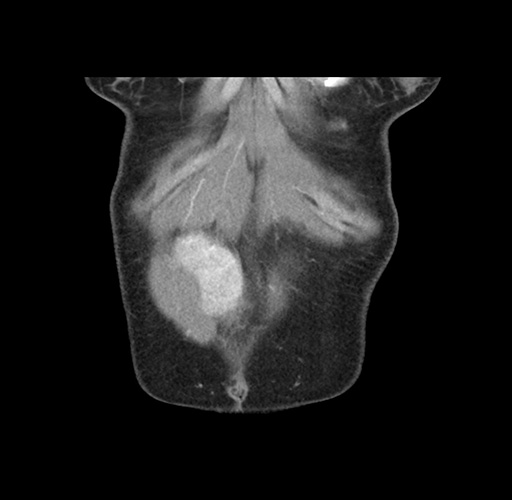

Imaging Analysis

Look through the patient's CT scan to identify any areas of concern for the necessary procedure.

Based on your CT findings, which issue(s) would give reason for "planned slowing down moment(s)" in this case?

Considering a standard left lateral sectionectomy procedure, what step(s) of the operation would you do differently in this case ?